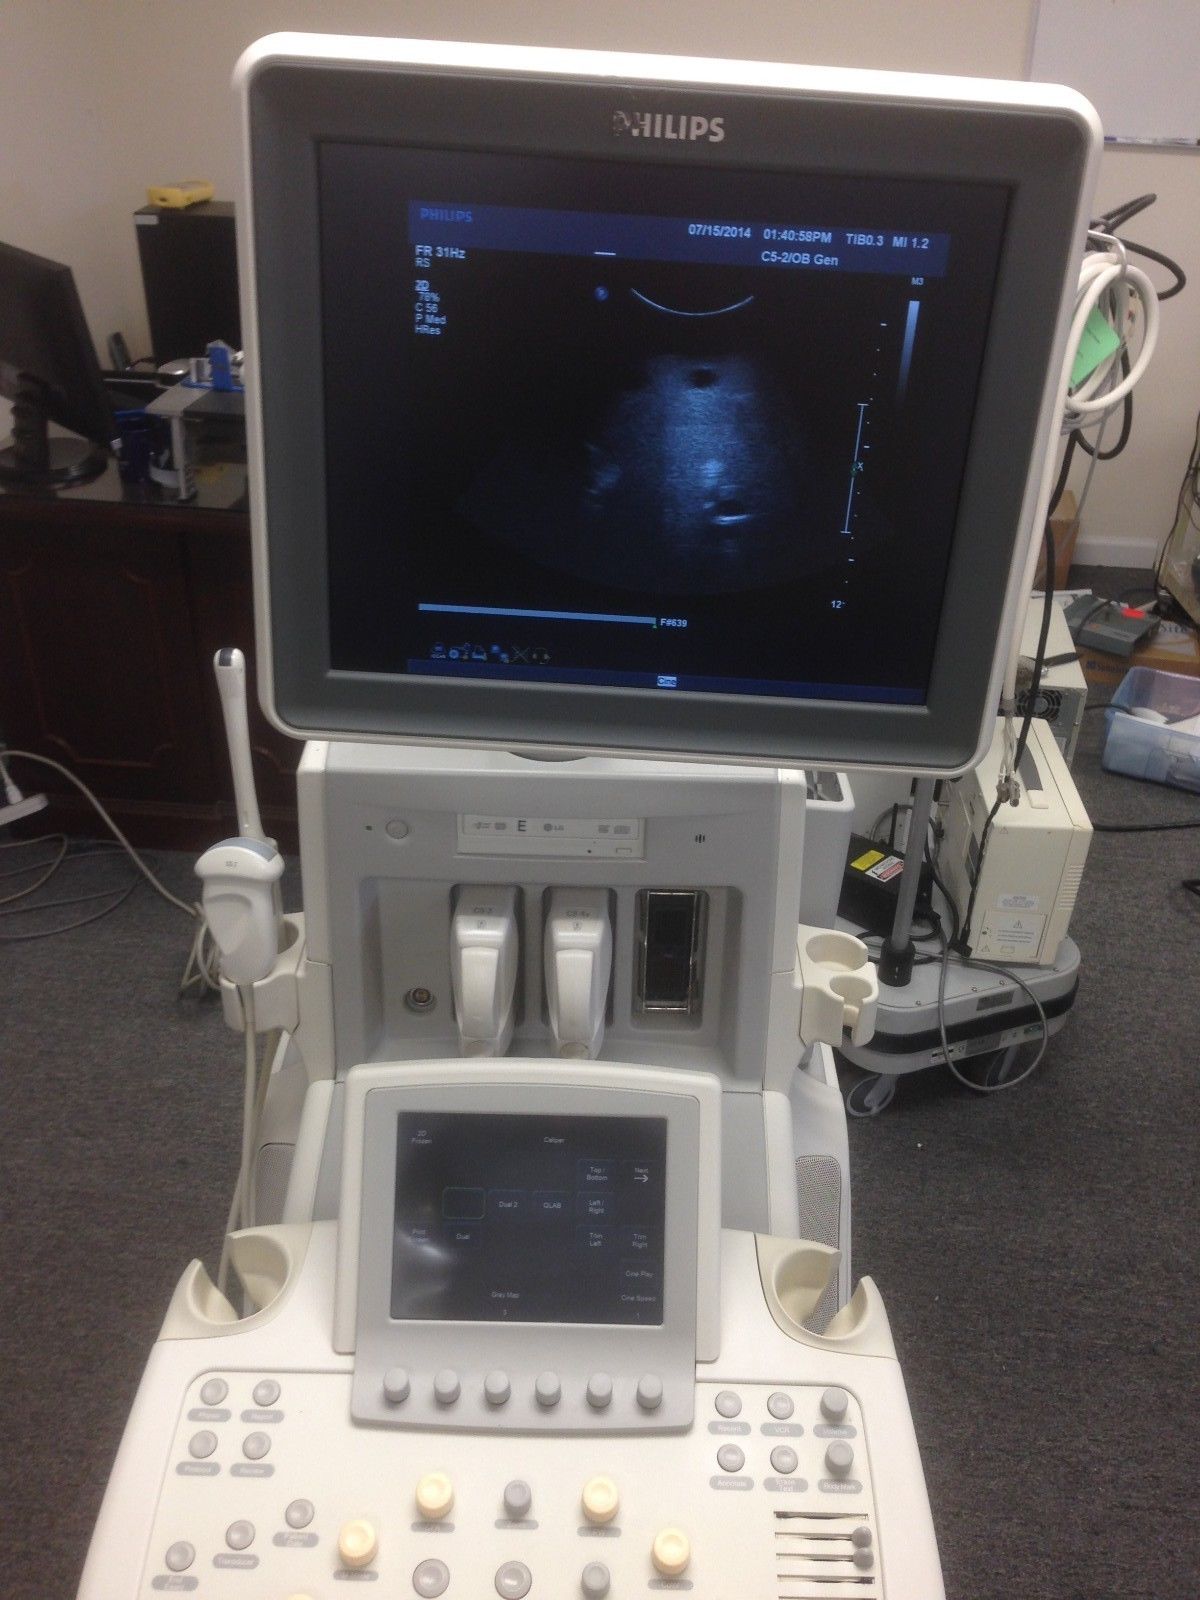

Philips Probes

DIAGNOSTIC ULTRASOUND MACHINES FOR SALE